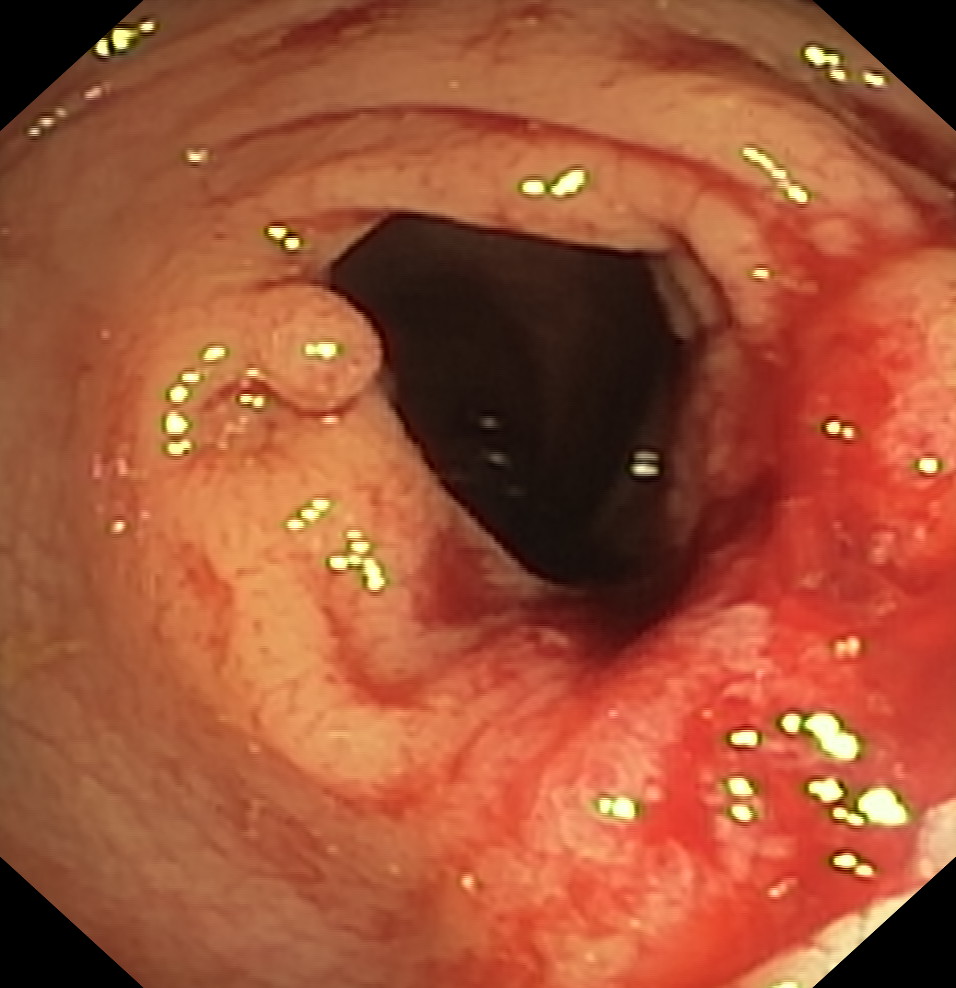

Nowotwory przewodu pokarmowego